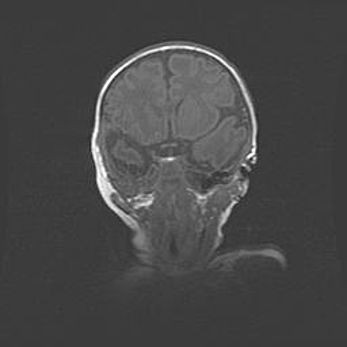

Множественные кисты обоих полушарий головного мозга, наибольшая из них в правой затылочной области. Ассиметричная атрофическая гидроцефалия.

Возраст: 7 месяцев

Вес: 5660 г

Пол: мужской

Окружность головы: 41,5 см

Срок гестации: 28-29 недель

Кисты головного мозга развиваются в результате многоочаговых некрозов вещества мозга и возникают вследствие перенесенной перинатальной инфекции, менингитов, энцефалитов, асфиксии, родовой травмы, расстройств мозгового кровообращения различного генеза. Образованию кист в веществе головного мозга плодов и новорожденных способствуют такие факторы, как высокое содержание в нем воды, недостаточная (или отсутствие) миелинизация и слабая астроглиальная реакция на повреждение.

Кисты могут сочетаться с гидроцефалией и другими поражениями головного мозга.